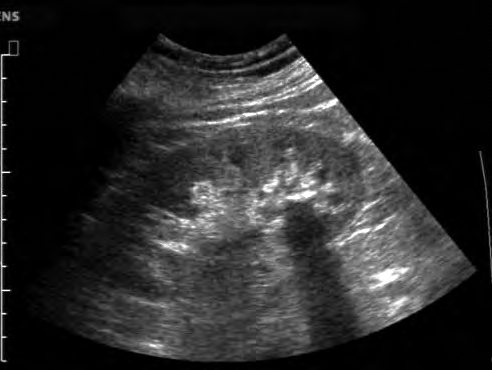

Na obrazie ultrasonograficznym jamy brzusznej uwidoczniono

A. naczyniaka wątroby.

B. kamicę nerkową.

C. pęknięcie wątroby.

D. kamicę żółciową.